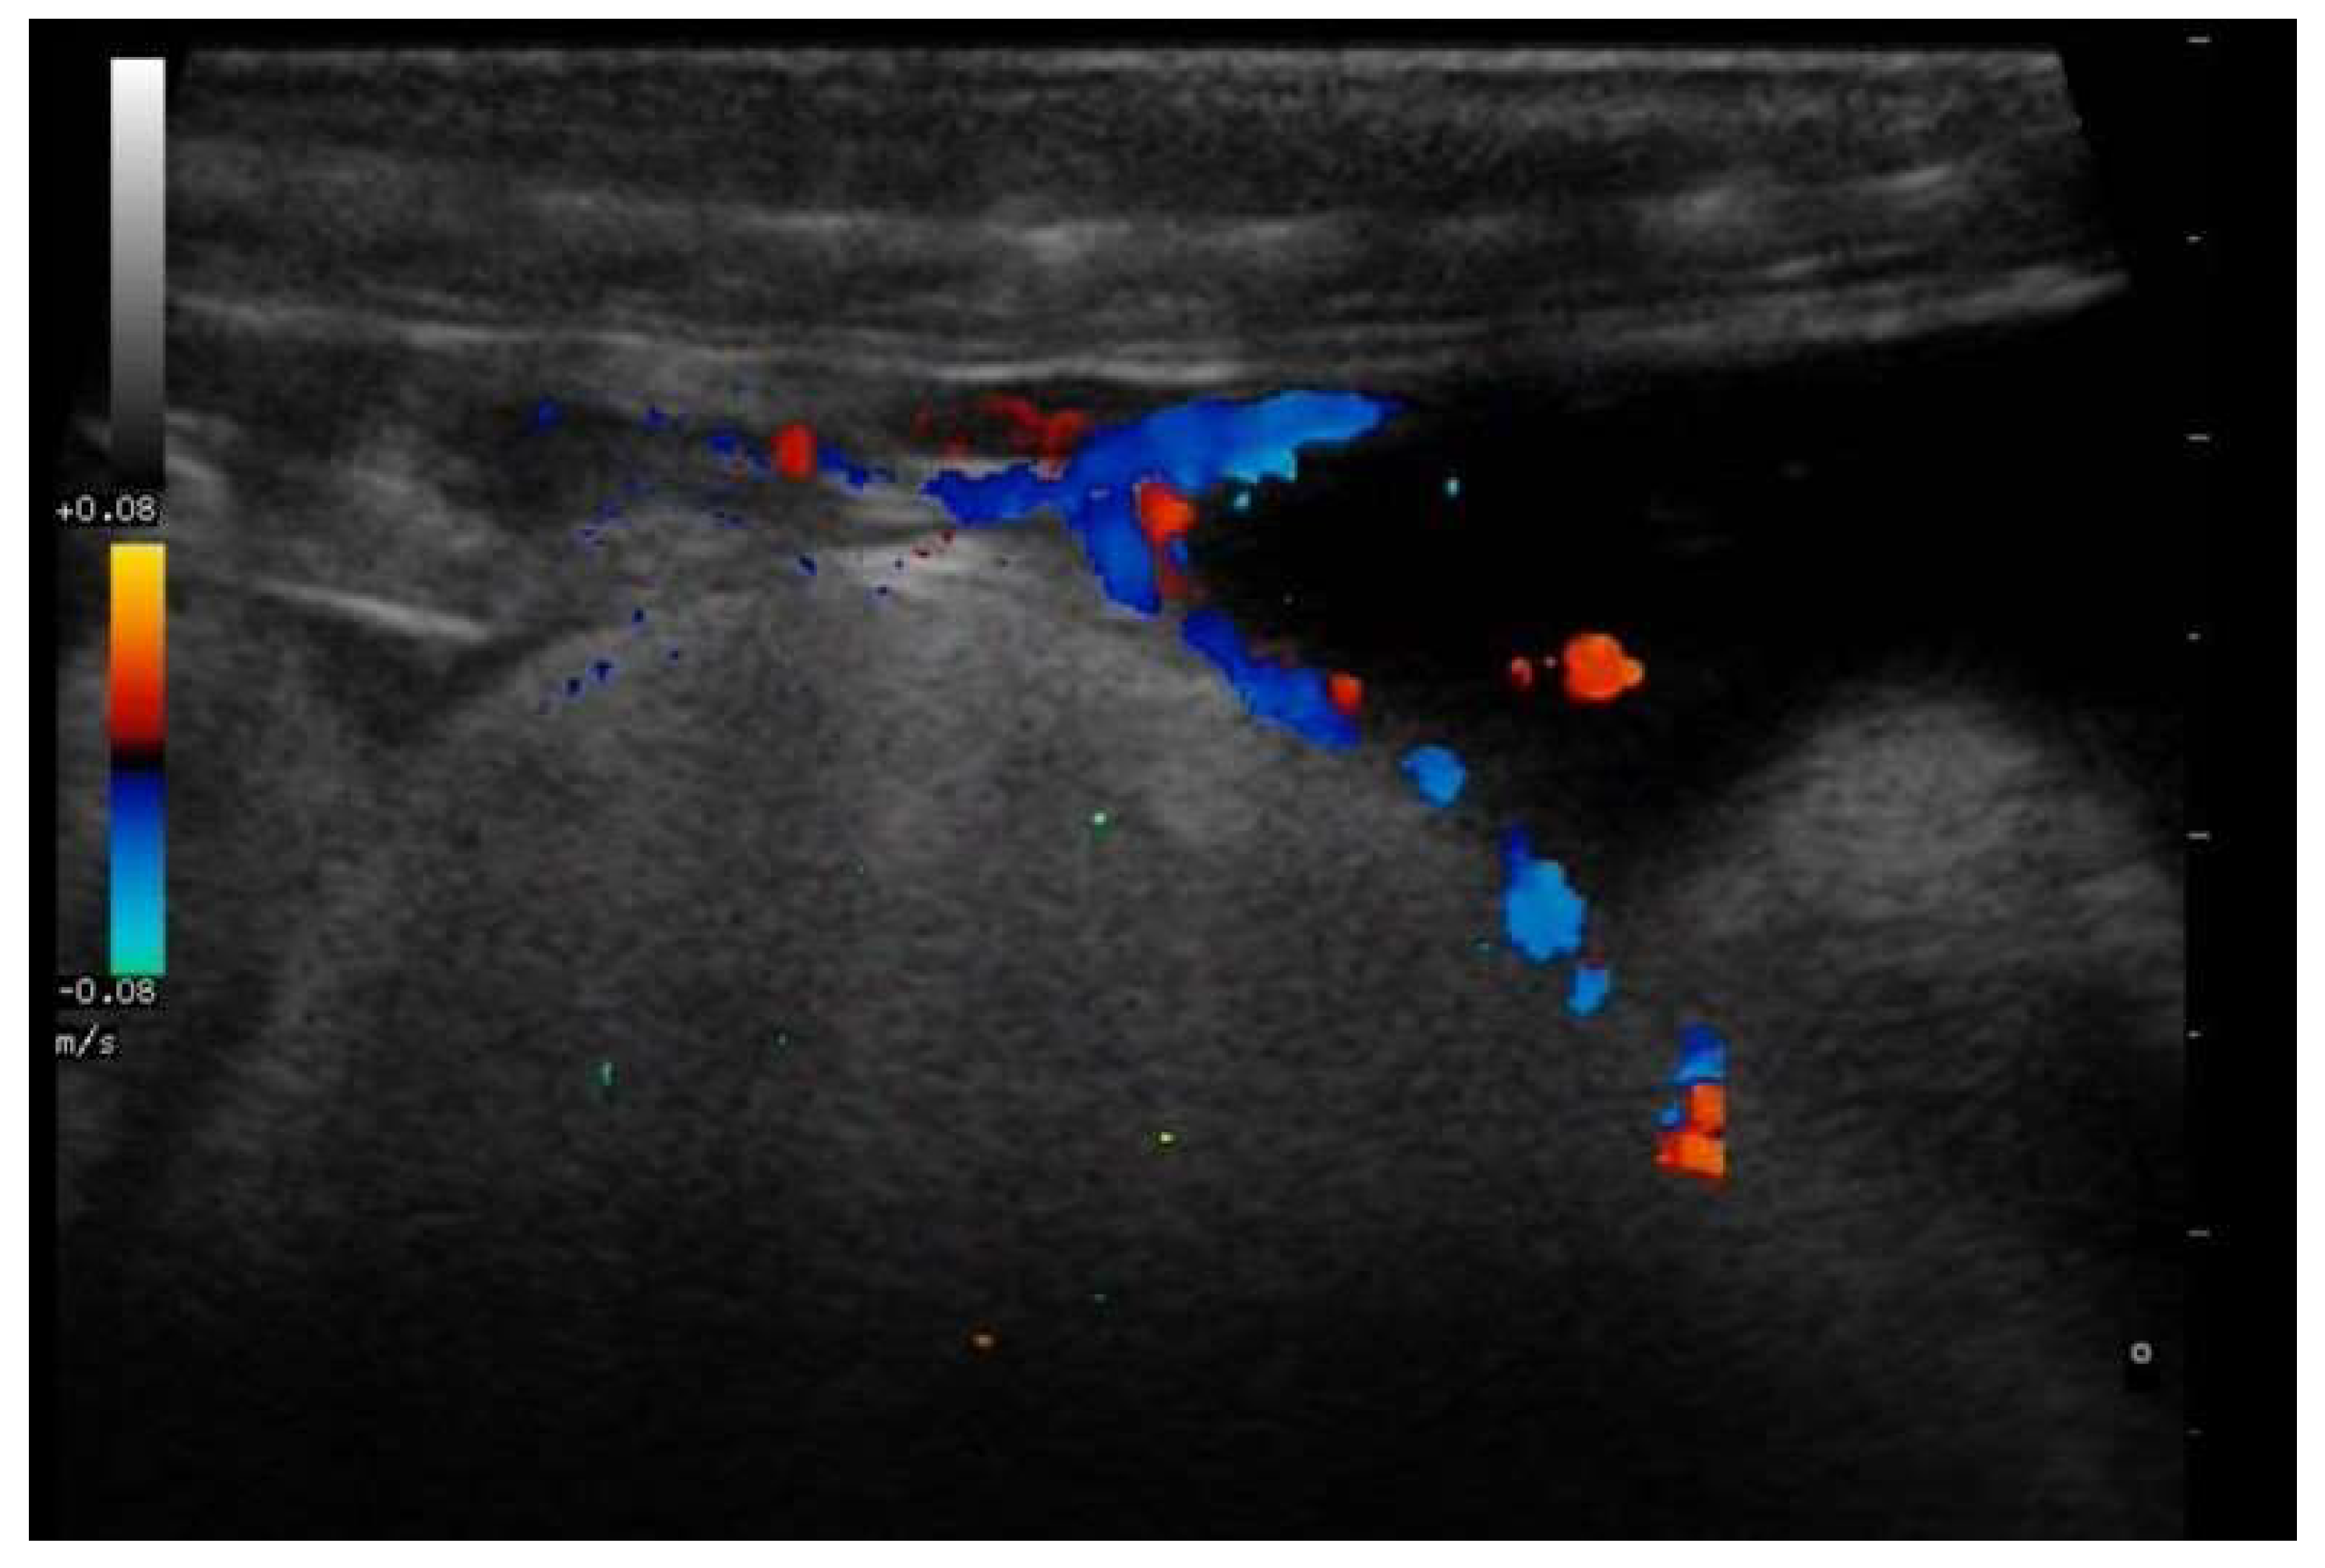

- Garcia, V.C.; Almeida-Santos, S.M. Reproductive cycles of neotropical boid snakes evaluated by ultrasound. Zoo Biol. 2021, 1–10. [Google Scholar] [CrossRef]

- Bigliardi, E.; Denti, L.; De Cesaris, V.; Bertocchi, M.; Di Ianni, F.; Parmigiani, E.; Bresciani, C.; Cantoni, A.M. Colour Doppler ultrasound imaging of blood flows variations in neoplastic and non-neoplastic testicular lesions in dogs. Reprod. Domest. Anim. 2019, 54, 63–71. [Google Scholar] [CrossRef]